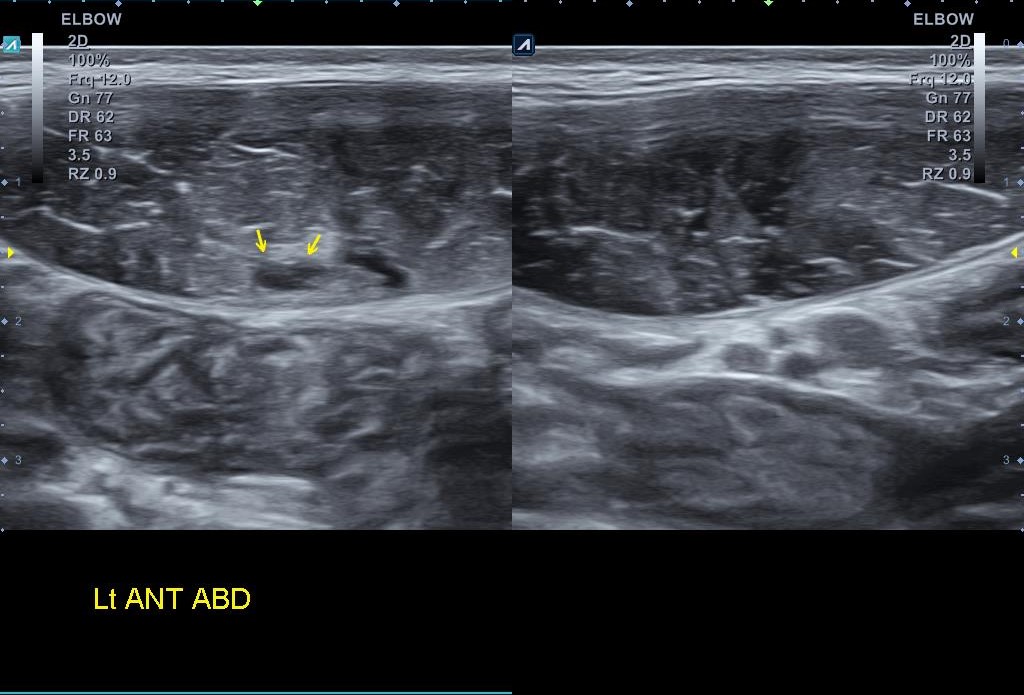

[박상준원장/통증이야기] - 배가 아프다고 온 배드민턴 선수 이야기(1) 나 : 시합은 나가셨어요? 복부 통증은 좀 어떠세요?환자 : 원장님.... 시합도 망쳤고... 무엇보다 통증이 훨씬 심해졌어요 ㅜㅜ나 : 연습하다 다시 통증이 생긴거에요? 아니면 시합중에?환자 : 시합에 나가기 위해서 연습은 거의 안했구요... 시합에 나가서 첫 게임에 스매싱하다가 갑자기 배에서 '뻑' 소리가 나서 쓰러졌어요...나 : 그래서 어떻게 됬어요?환자 : 어찌어찌 시합은 마쳤는데.... 배에 멍도 들고 무엇보다 배가 너무 아파요 ㅜㅜ 무조건 시합은 뛰어야 한다고 했던 환자.. 부상과 통증을 참고 어쩔 수 없이 시합에 참가한 후 부상이 심해진 걸로 보입니다. 좌측 하복부에 압통은 좀 더 심해져 있었고 주변에 멍까지 든걸로 ..